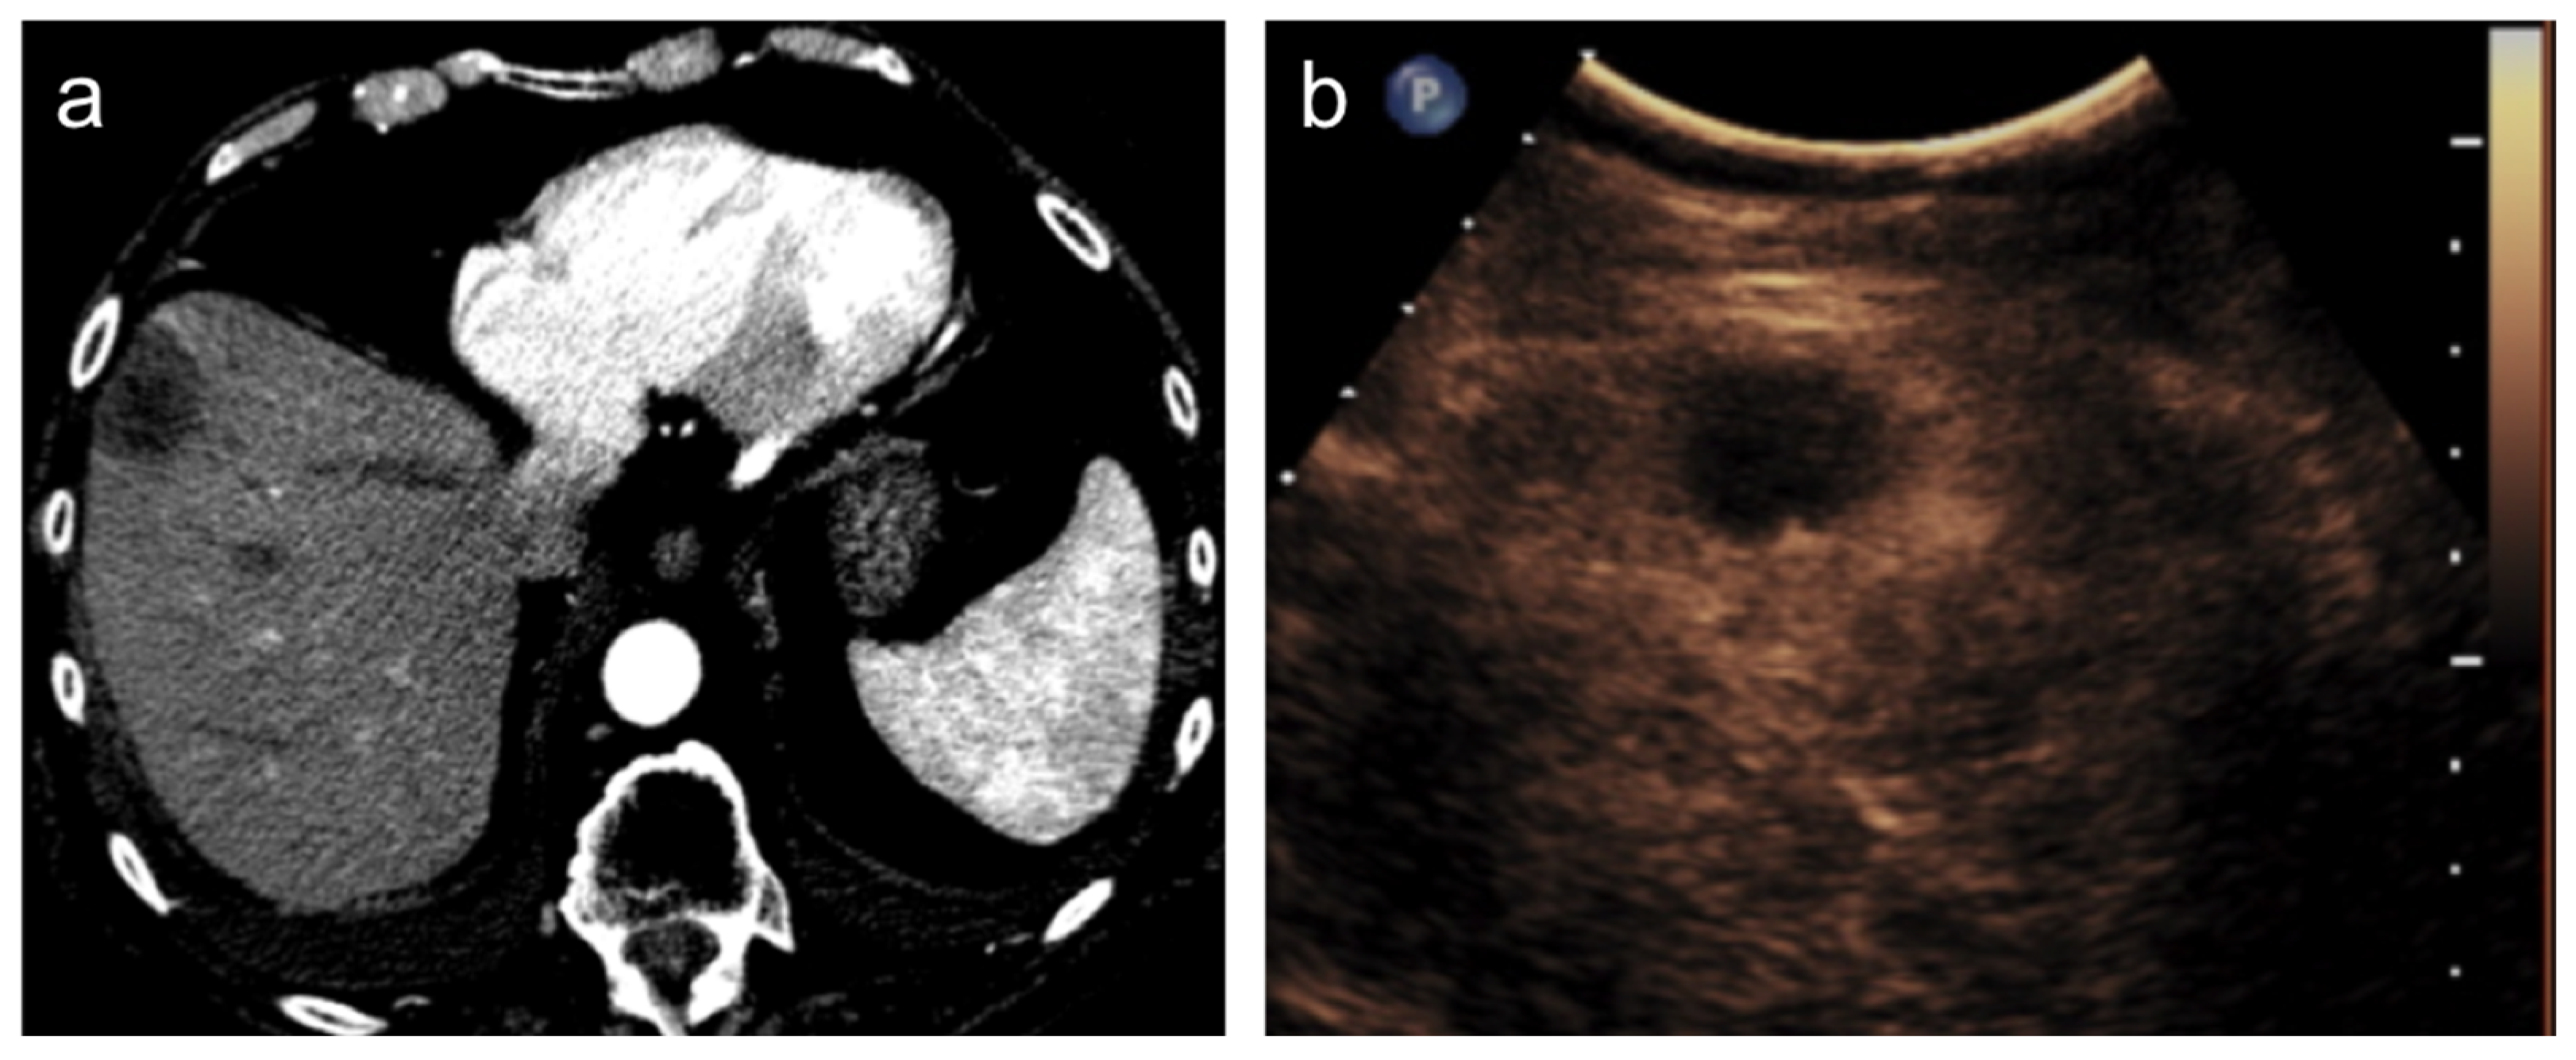

3. Treatment Response Criteria